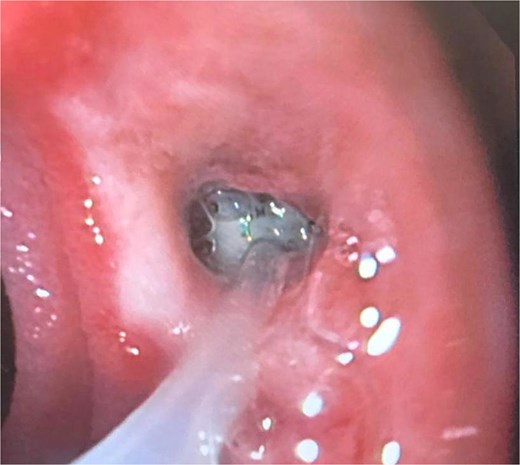

A 44-year-old female with no significant medical history underwent Roux-en-Y gastric bypass for grade III obesity (BMI 41). She presented with necrosis of the gastric pouch within the first 48 hours, leading to leakage of the gastrojejunal and jejunojejunal anastomoses. Esophagojejunal anastomosis and revision of the jejunojejunal anastomosis were performed, but the patient developed septic shock due to esophagojejunal anastomosis leakage, requiring 7 days in intensive care. Upon stabilization, she was referred to our service for endoscopic management of an esophagojejunal fistula. A 10 mm fistulous orifice was observed (Fig. 1), and EVAC therapy was initiated using a polyurethane sponge with an 8 Fr catheter at 125 mmHg continuous suction (Fig. 2). Six changes were made at 3–5-day intervals.

The placement of the catheter and sponge for EVAC therapy is observed.